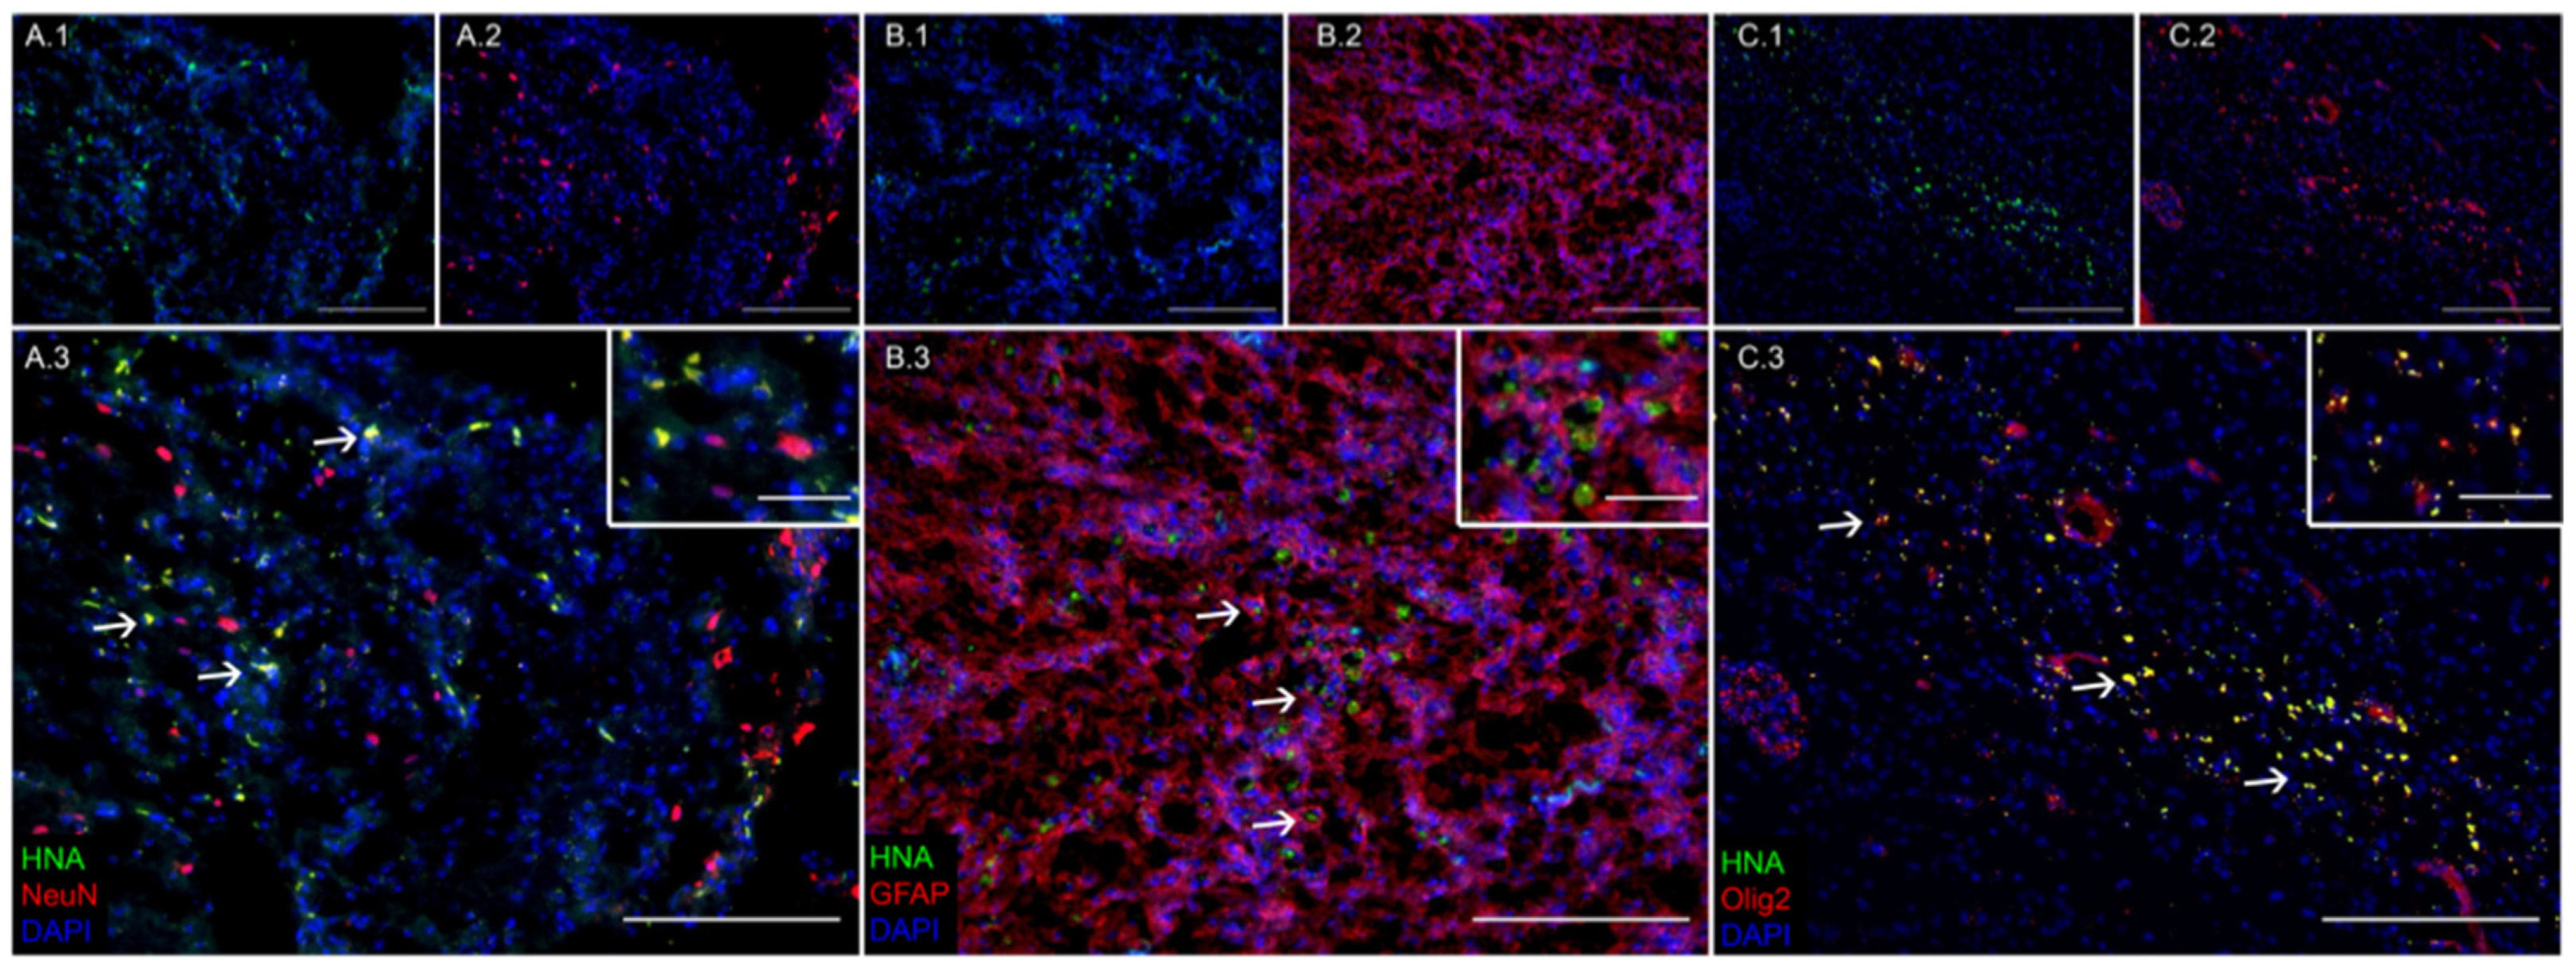

3.1. Transplanted iNSCs Survived Long-Term and Differentiated into Neurons, Astrocytes, and Oligodendrocytes